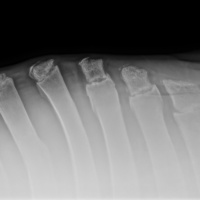

RADIOLOGIA DIGITALE AD ALTA DEFINIZIONE

Cuattro DR HD è l'ultimo sistema radiografico digitale ad alta definizione per piccoli animali ed equini prodotto dal fornitore leader di soluzioni radiografiche digitali veterinarie.

Innovativo, veloce, efficace, sicuro e ancora più brillante: l'ultimo sistema a raggi X, Cuattro DR HD soddisfa i più alti standard nella diagnostica radiografica veterinaria.

- Visualizza i dettagli come mai fino ad ora : 17x17'’ 100 microns High definition detectors combinati con la migliore tecnologia post-elaborazione nel nostro software per immagini di altissima qualità